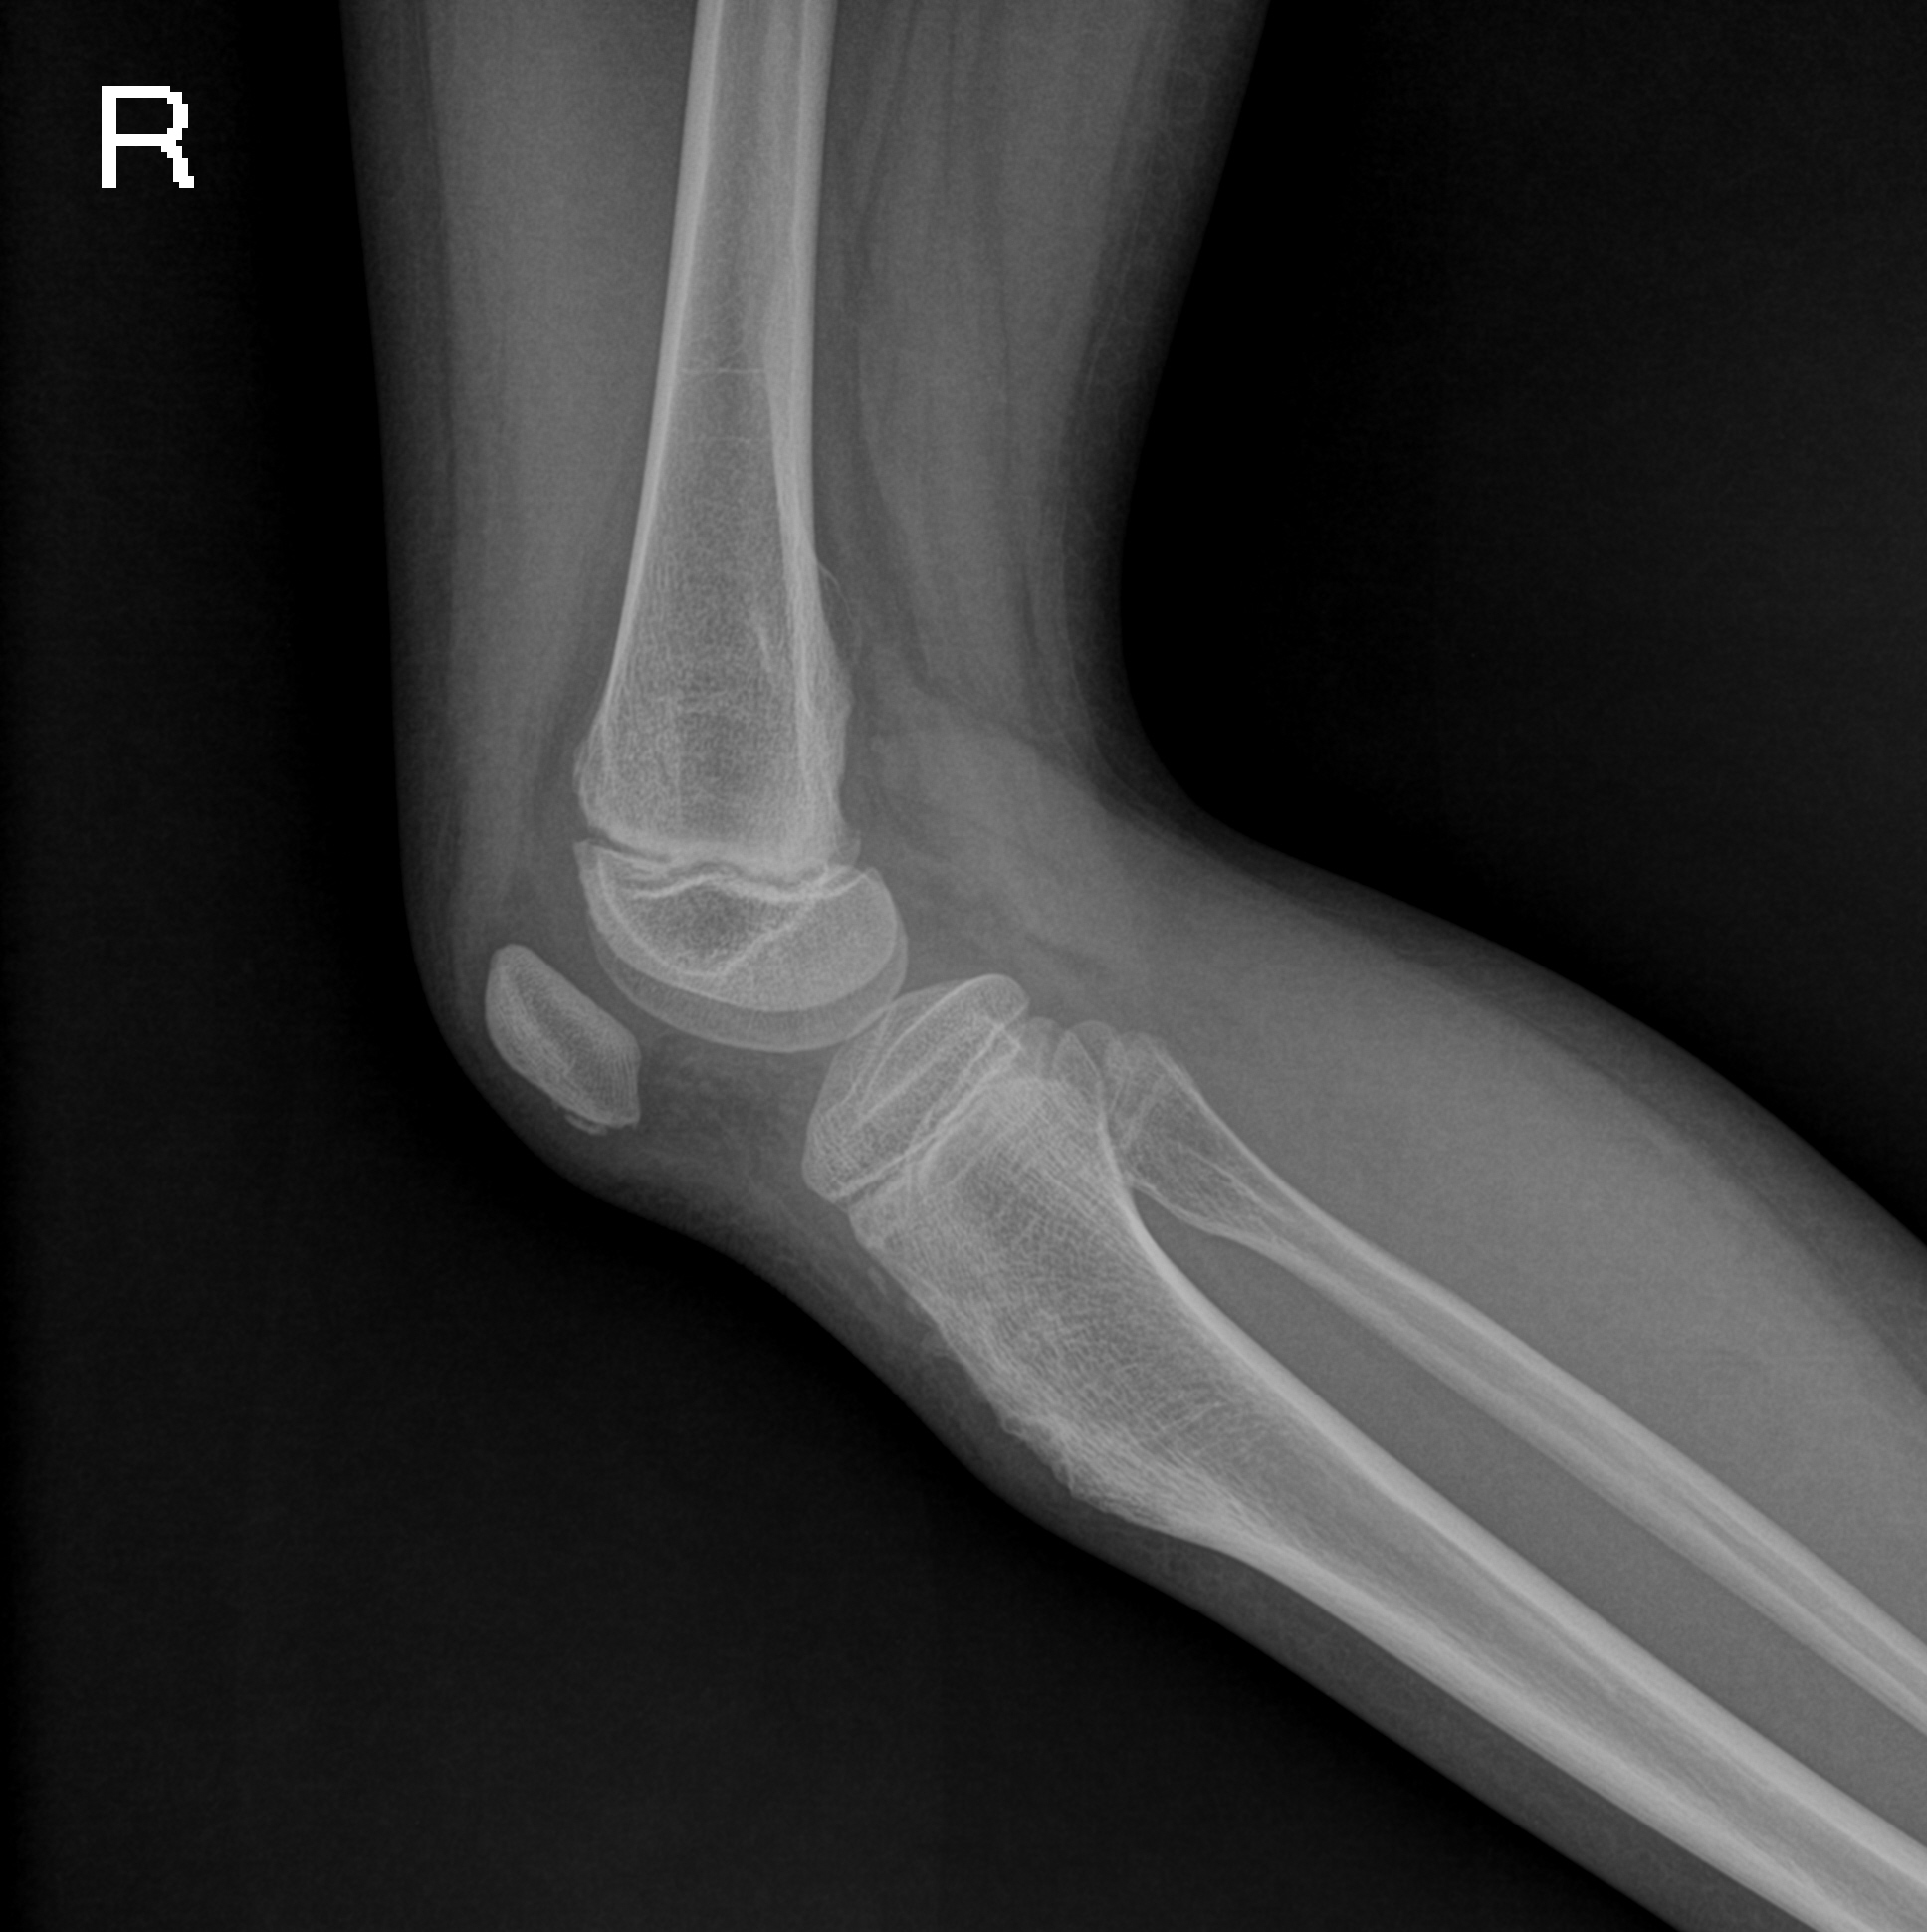

PED5407:右胫、腓骨上段良性病变,请会诊!

女,10岁,发现右胫骨近端肿痛数月,右小腿近端可见包块;DR示:右胫骨结节骨质增厚、毛糙,腓骨头稍膨大,MR示:未见明显骨质破坏,周围见少量积液,未见软组织肿块,胫骨结节骨软骨炎?腓骨干骺端良性病变? ...

考虑:右股骨下段及胫骨上段骨软骨瘤病。右膝关节囊少许积液。

1)右侧股骨下段及右侧胫腓骨上段多发性骨软骨瘤(即骨软骨瘤病)。2)右膝关节少量积液。